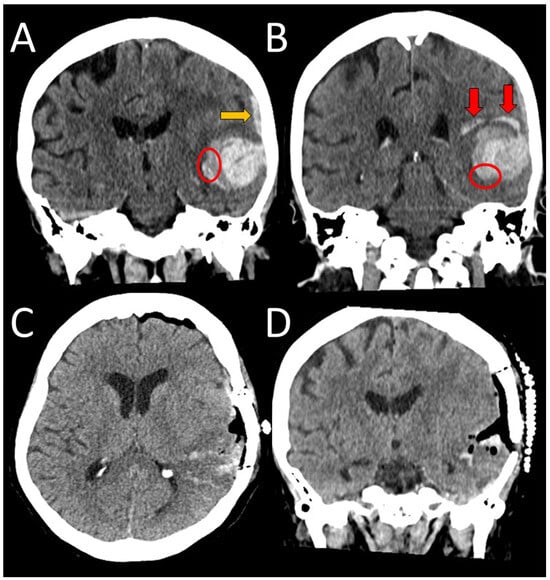

A 63-year-old right-handed female, with a history of a severe TBI at an age of 21, without consequences (premorbid mRS 0), presented to NED, UMC Ljubljana, in January 2025 with an acute headache and vomiting, followed by a rapid decline in consciousness to coma (Glasgow coma scale, (GCS) 3). She was analgosedated, intubated, and mechanically ventilated in NED. Her arterial blood pressure was 160/90 mmHg and ECG and laboratory tests were unremarkable. An urgent head CT scan revealed an ICH in the right hemisphere, accompanied by an SDH and transtentorial herniation (Figure 3A). Urgent surgical evacuation of ICH was performed, and the bone flap had been removed and stored for future return (Figure 3B). A cortical biopsy identified Aβ deposits in the blood vessel walls, confirming the CAA (Figure 4). She was subsequently transferred to the ICU. Analgosedation was discontinued on the seventh day after admission. However, 21 days after the initial hemorrhage, her condition deteriorated—she presented with severe left-sided paresis and somnolence. A follow-up CT scan (not shown) revealed a recurrent ICH at the previous hematoma site, measuring 8.3 × 3.2 × 3 cm, with right-sided transtentorial and a more pronounced transcranial herniation. Therefore, a second surgical intervention was performed. After several days, a third hemorrhagic event with a smaller ICH occurred in the region of previously treated ICHs, but she remained asymptomatic (Figure 3C). Over time, her motor deficits significantly improved, but cognitive impairment, including apraxia, disorientation in time, and disturbed visual–spatial functions, was observed. Her rehabilitation continued on an outpatient basis (Figure 3D).

Figure 3. An axial view of a spontaneous ICH in the right occipitoparietal region measuring 6 × 5 × 6 cm, with pronounced brain edema and midline shift (white arrows). The red arrow indicates finger-like extensions in the brain parenchyma. The orange arrows indicate SAH and subdural hematoma (A). Postoperative CT scan shows good surgical evacuation of the bleeding, with a removed bone flap (B). A week after the second surgery (not shown), a smaller bleeding occurred (orange star), which was treated conservatively (C). A few weeks after the second surgery, the brain edema had subsided, and the patient was transferred to a rehabilitation unit. The bone flap has not yet been replaced (D). The ellipse denotes the area of surgical biopsy.